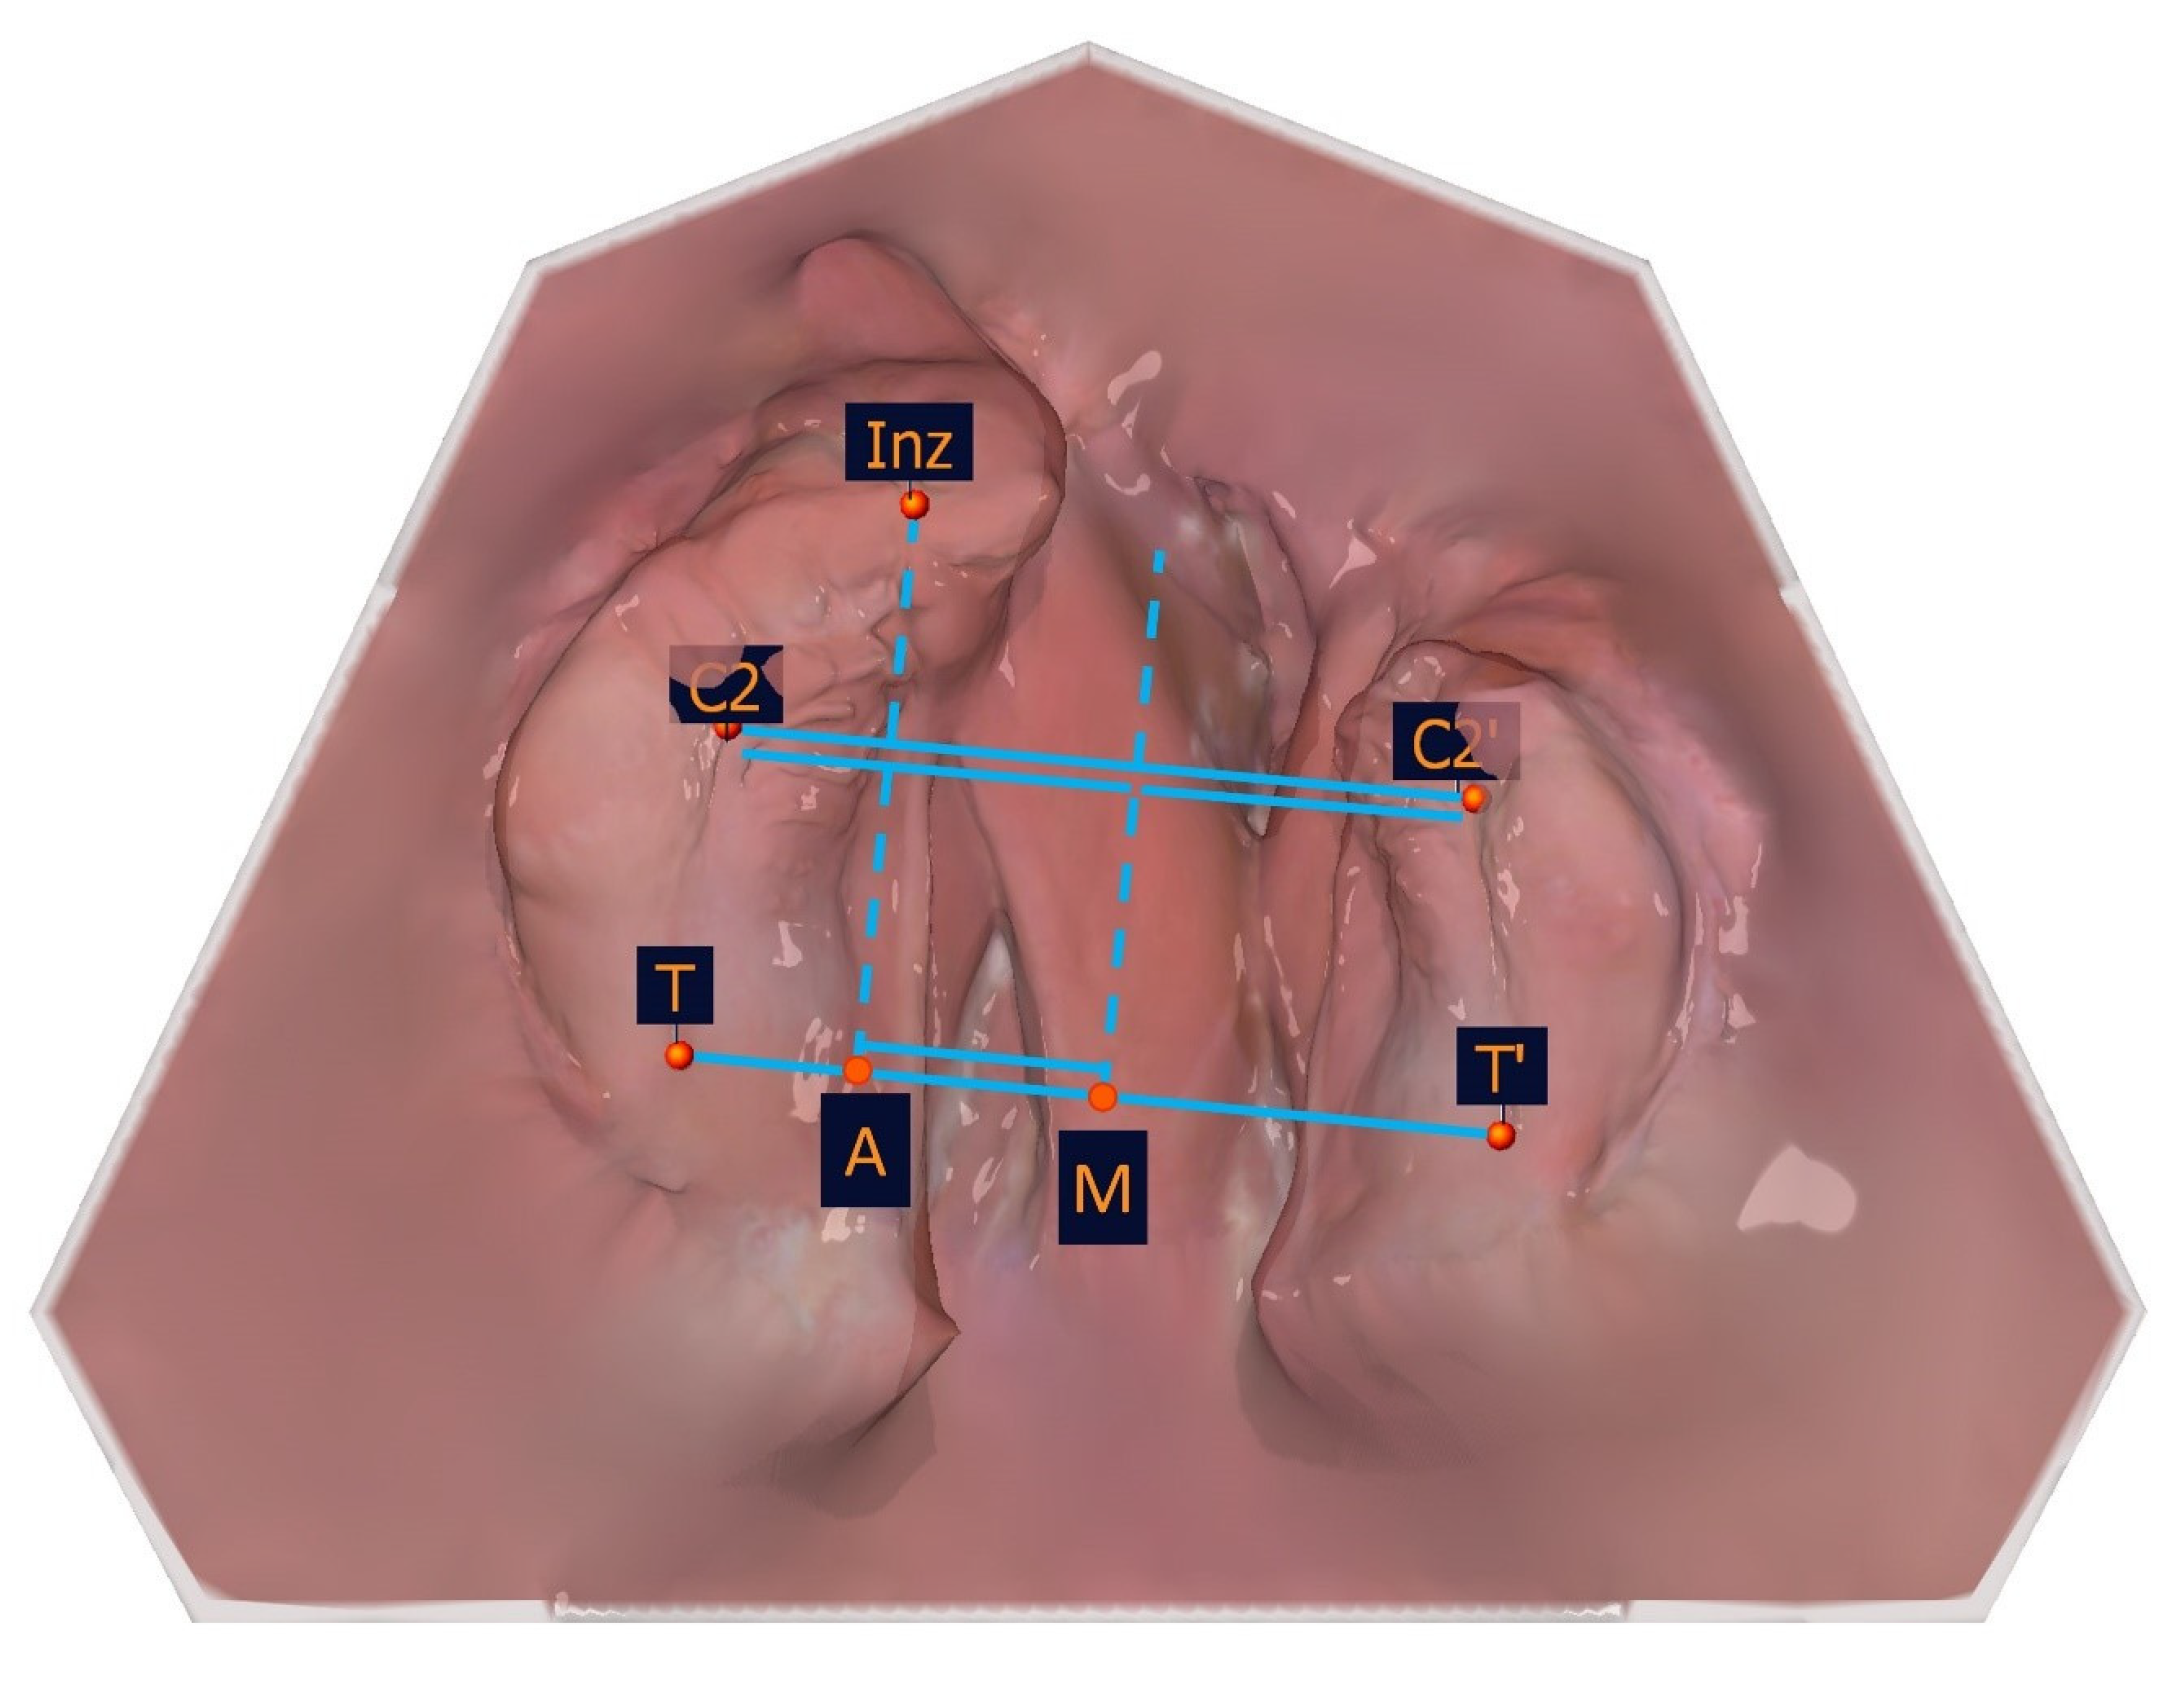

The measurement points of the alveolar cleft width are shown in Table 4 and Figure 7.

The segment length measurements are shown in detail in Table 4 and Figure 8.

The large and small segments were divided into subsegments to identify the transversal landmarks (T-C2, C2-Inz, and Inz-P1 for the large segment and P2-C2′ and C2′-T′for the small segment). The most vestibular and most palatal points in each section were determined. For the segmental width measurements, the greatest distance perpendicular to the length measuring sections of the partial jaw segments defines the greatest width of the jaw segments. The segment width measurements are shown in Table 4, and an exemplar is shown in Figure 9.

Figure 5. Illustration of the segmental width measuring measurement points of the partial jaw segments. The segmental width measurement points and their description are presented in Table 2.

Figure 9. Exemplary illustration of the segment width measurements.